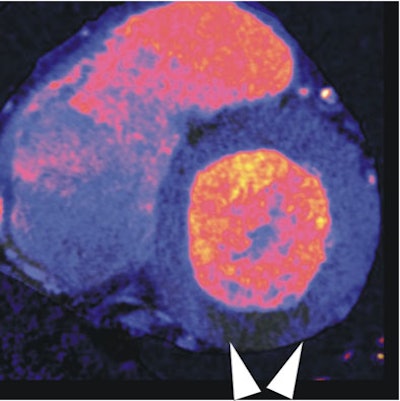

![]() |

| In a 64-year-old man with chest pain, colored regions of blood-pool images represent iodine, while the darker parts of the myocardium depict ischemia as a lack of contrast uptake. Arrows indicate the myocardial blood-pool deficit, i.e., ischemia. |